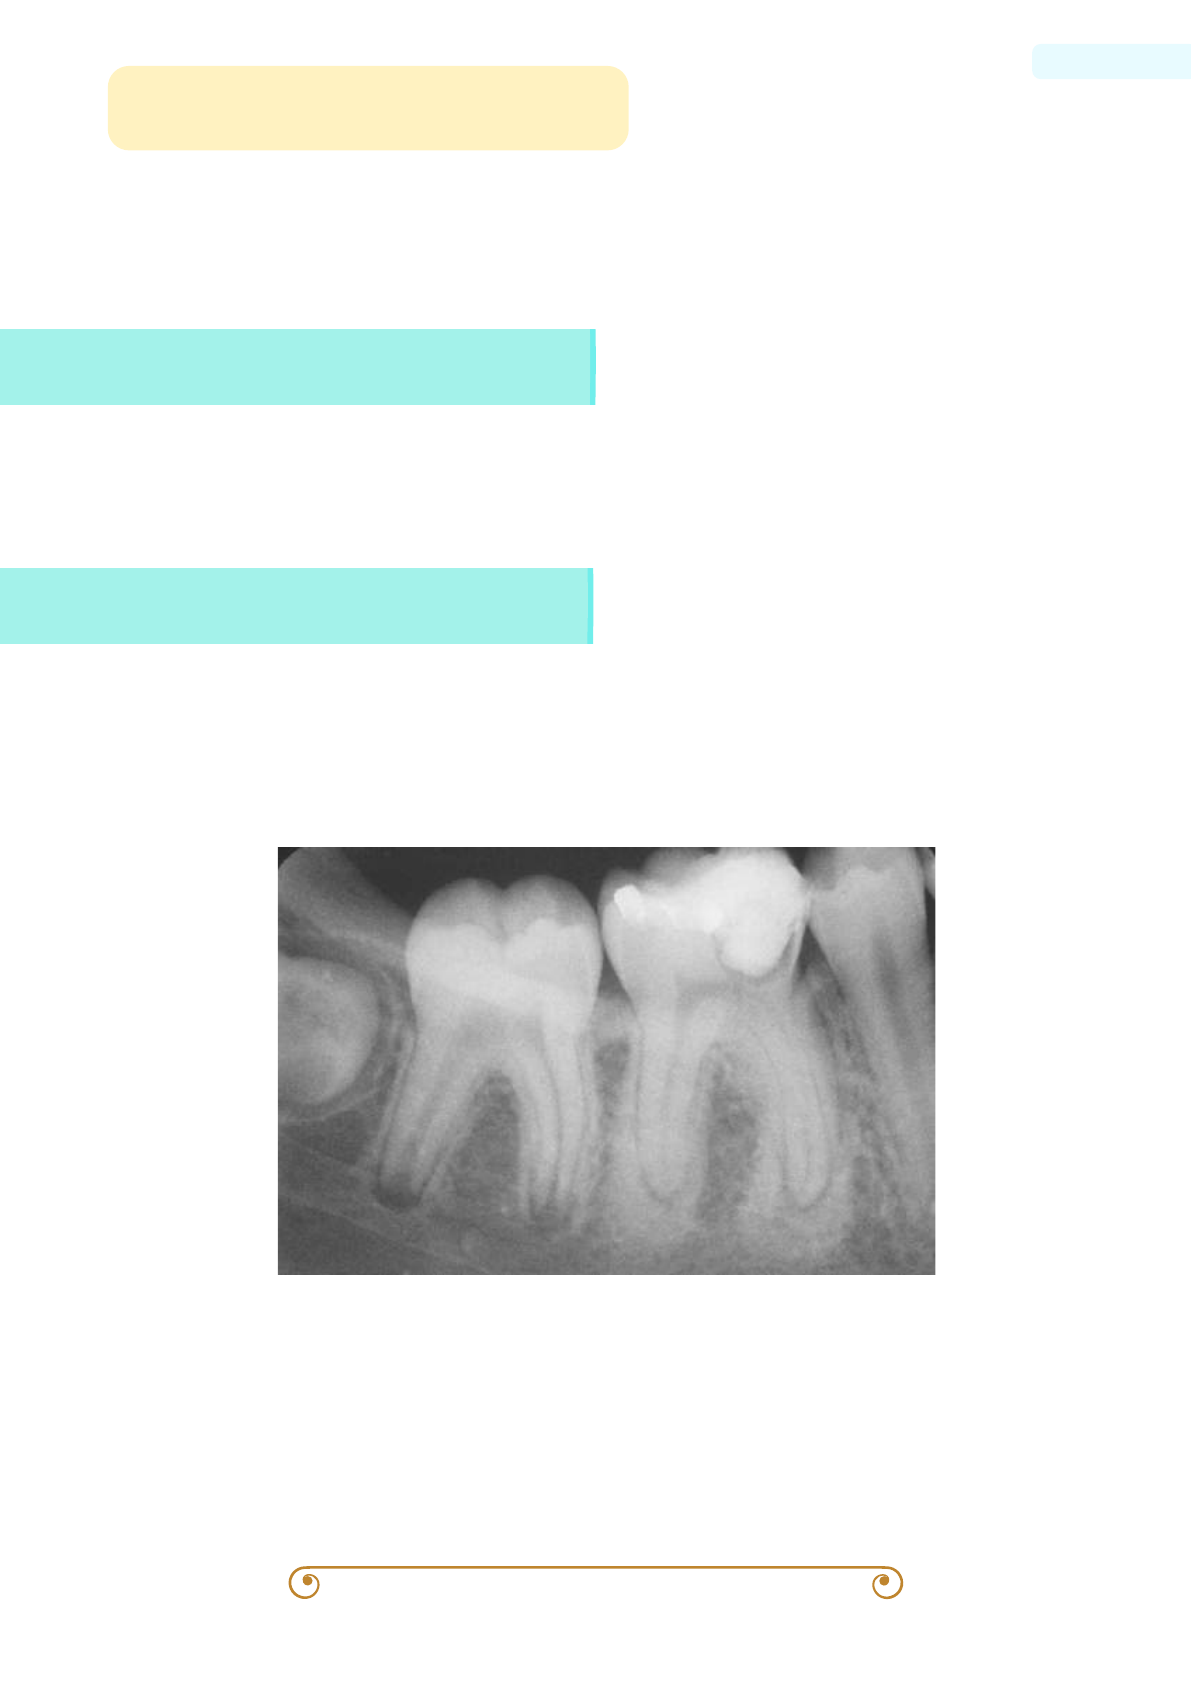

image size: 1191x1684

Grátis: Osteíte condensante osteomielite esclerosante focal | Conceito, Características Clínicas, Tratamento e Prognóstico | Patologia Oral - Material Claro e Objetivo em PDF para Estudo Rápido